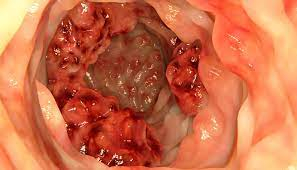

Campanha Maio Roxo alerta sobre doenças inflamatórias intestinais

A campanha visa alertar a população e também os médicos sobre essas doenças, cuja prevalência aumentou 15% entre 2012 e 2020, conforme estudo feito por pesquisadores da Pontifícia Universidade Católica do Paraná com 212 mil pacientes do Sistema Único de Saúde (SUS).